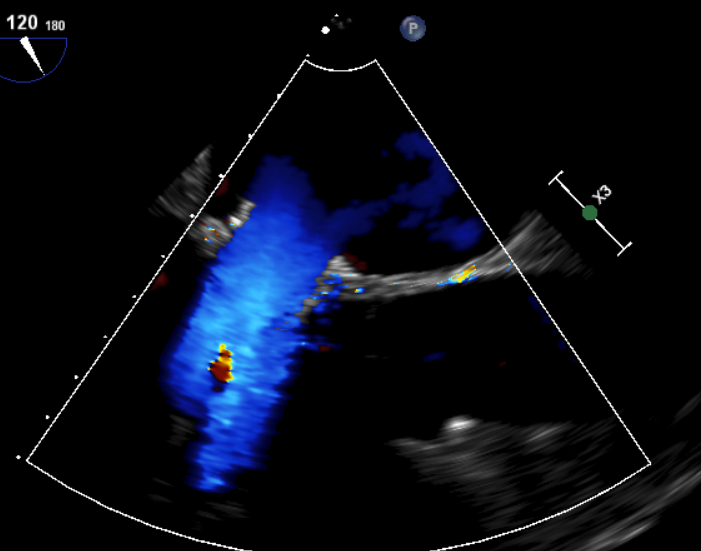

原生物瓣少量反流

过瓣流增快,呈“五彩状”

CDFI提示过瓣血流通畅

CDFI示少量瓣周漏